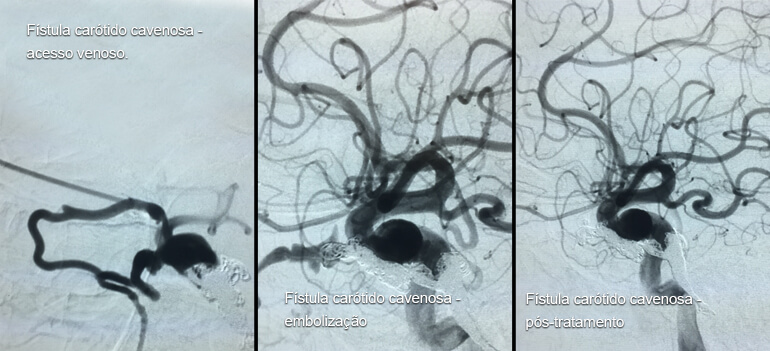

Fístula carótido cavernosa

Fístula carótido cavernosa corresponde a comunicação anômala entre a porção intracavernosa da artéria carótida interna e o seio cavernoso. O seio cavernoso (estrutura venosa), habituado a regimes de baixa pressão sanguínea, passa a receber sangue com regime de pressão arterial, que é transmitida retrogradamente para veias orbitárias, com conseqüente proptose pulsátil (projeção do olho, que pulsa conforme o batimento cardíaco), quemose (vermelhidão) e baixa da acuidade visual. Se a drenagem venosa ocorrer para as veias intracranianas torna-se considerável o risco de hemorragia intracraniana.

A fístula carótido cavernosa está mais freqüentemente relacionada a traumatismo craniano pregresso ou ruptura de um aneurisma intracavernoso da artéria carótida interna. Essa patologia é considerada uma urgência médica pois pode levar a perda visual definitiva e hemorragia intracraniana.

A via endovascular é a primeira escolha para o tratamento.